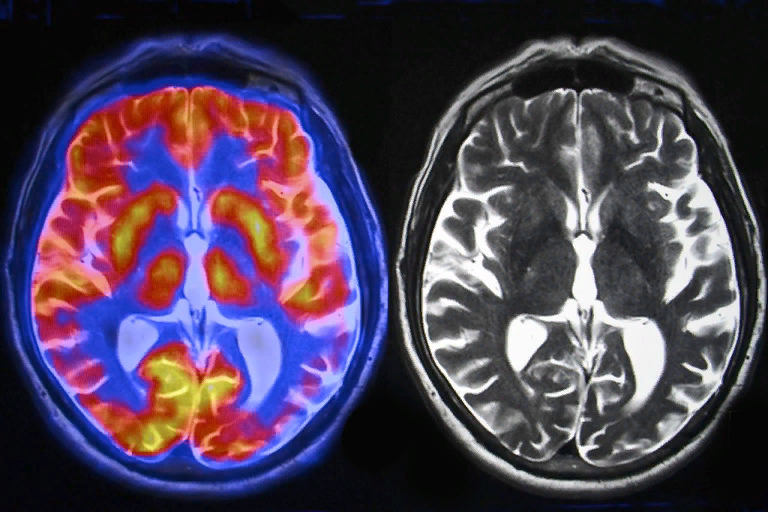

МРТ – магнитно-резонансная томография. Применяется, как правило, для выявления болезней, опухолей, в общем – в целях лечения и профилактики головного мозга. МРТ также показывает и зоны наибольшей активности мозга в данный конкретный момент.

МРТ показывает, что мозг работает всегда и весь. Отличается лишь активностью некоторых областей. Когда вы спите, головной мозг осуществляет свою деятельность в упрощённом режиме, по сравнению с бодрствованием. Все функции сведены к минимуму, по сути, нам необходимо только дышать и гонять кровь, даже обмен веществ, переваривание пищи, все замедляется. Во время сна выработка гормона роста вырабатывается в 5 раз больше, а кто всем этим руководит..?